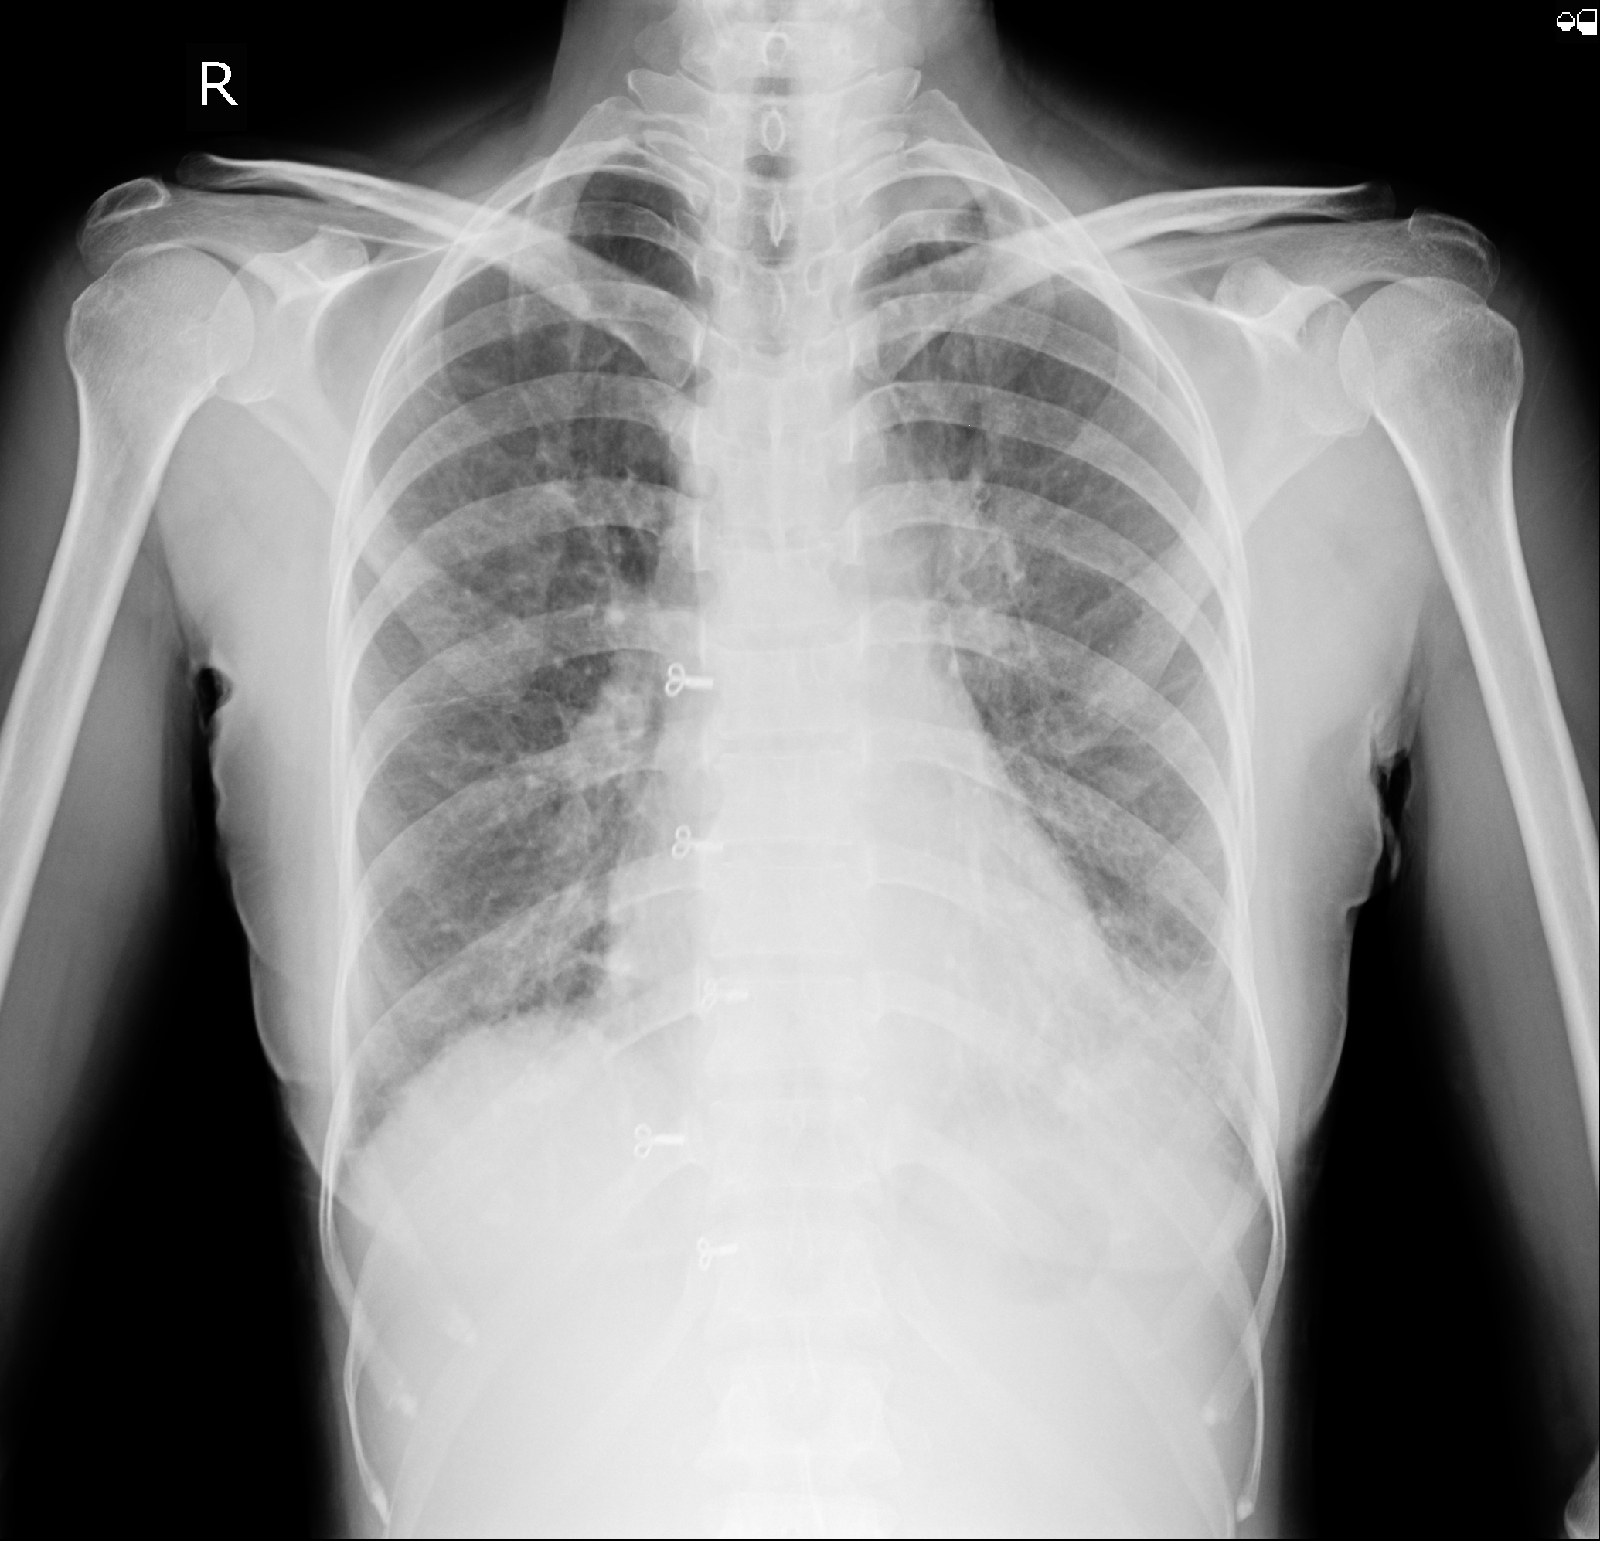

CHEST XRAY: